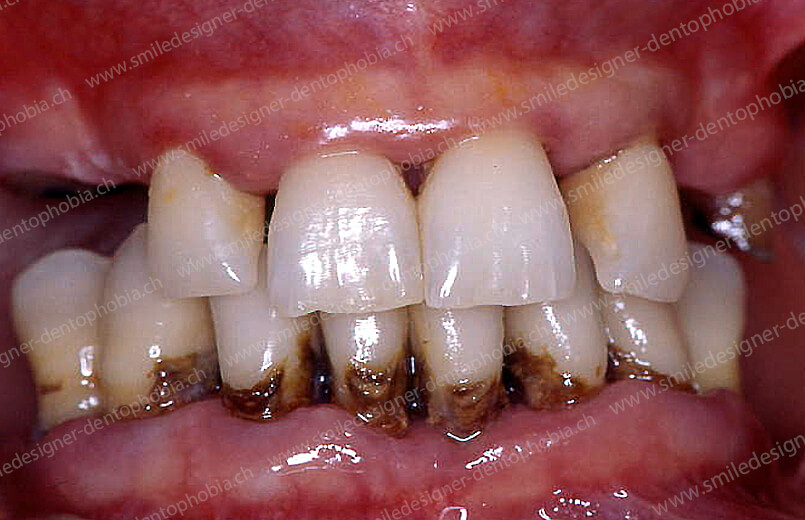

Cas clinique « GOLD DAMAGE CONTROL MCI » maxillaire : Bridge implanto-porté avec extensions postérieures (ALL ON 8). Version définitive des bridges avec un cosmétique en céramique.

Face à une perte dentaire multiple, un traumatisme ou une usure sévère, le protocole Gold Damage Control offre une solution immédiate et complète pour restaurer un sourire en une seule intervention. Conçu pour les situations critiques où la qualité de vie et la confiance en soi sont menacées, ce protocole combine implants dentaires, bridges provisoires fixes et techniques innovantes pour redonner aux patients un sourire naturel, fonctionnel et durable, même dans les cas les plus complexes.

- Esthétique et fonction restaurées : les prothèses reproduisent le festonnage gingival naturel et offrent une occlusion parfaite, protégeant les articulations temporo-mandibulaires (ATM).